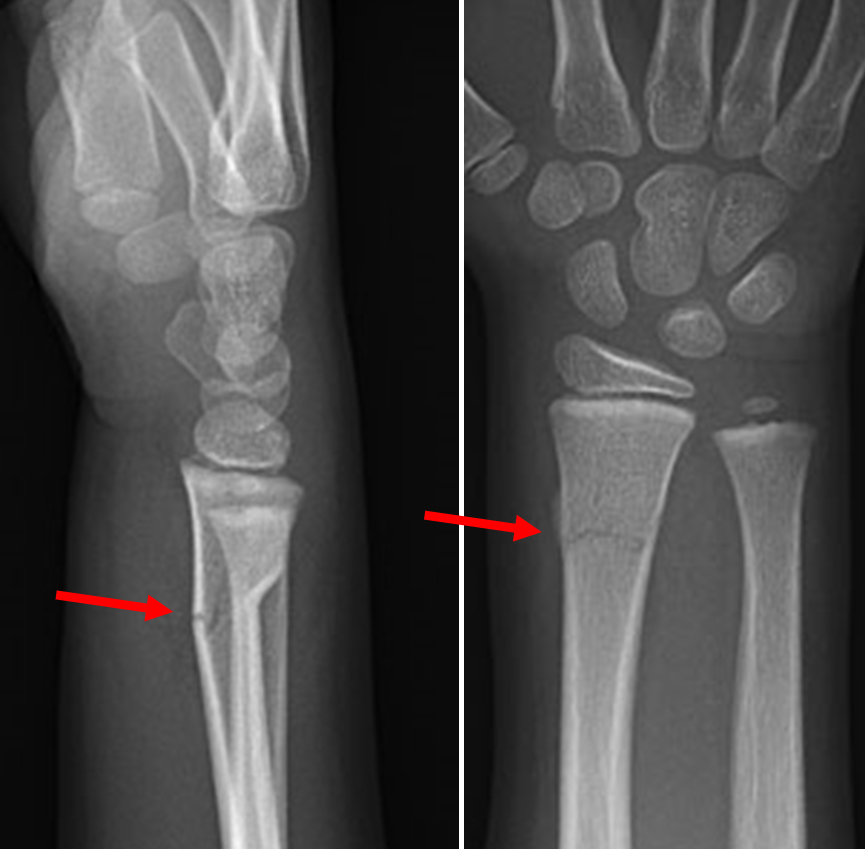

Example xray of greenstick fracture of distal radius:

(demonstrating extension of fracture line to volar cortex with angulation of the volar cortex)

Images from:

Royal Children's Hospital Melbourne - Greenstick fracture distal radius